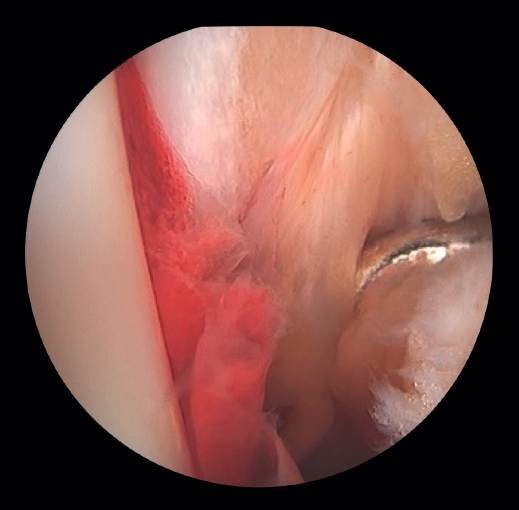

If the deltoid ligament injury involves only the anterior part, arthroscopic reinsertion can be made using resorbable implants. If deltoid ligament disinsertion is complete, open reinsertion is preferred, because of the difficulty of placing the implants in the posterior malleolus and the risk of neurovascular injury (Figure 5).

- Diagnosis of syndesmotic instability. Arthroscopy allows assessment of the integrity of the syndesmosis and the MCS on the radiograph and CT scan, especially in SER II and IV fractures. It has been shown that radiographic assessment is not always predictive of the syndesmotic lesion. In addition, arthroscopy ensures its anatomical reduction. Takao found that 87% (33/38) of the ankles with fractures had syndesmosis lesions detected by arthroscopy(20).

Arthroscopy allows both direct visualization and dynamic assessment of the syndesmosis(21,22).

- It makes it possible to differentiate between SER II fractures (where there should be no syndesmosis damage) and SER IV fractures, where the syndesmosis is affected and can be stabilized(5,23).

- Arthroscopy can avoid the false impression of a widened medial joint space on fluoroscopy due to congenital anomalies.

- Being able to visualize the malleolar incisura together with radioscopic control allows us to ensure correct positioning of the incisura fibularis, especially in patients with unstable injuries where there is a risk of malreduction due to shortening or rotation of the fibula(5,24).

- Arthroscopy can help avoid overcorrection of the syndesmosis, which is highly arthrogenic(5,24) (Figure 6).

Figure 6. A: syndesmosis injury; B: control of reduction to avoid overcorrection; C: intraoperative control of correct reduction of the fibula at the incisura.